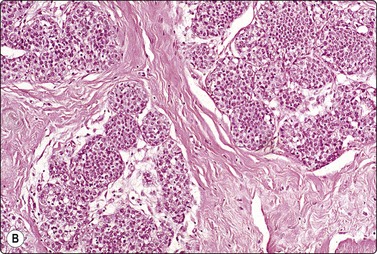

image image

Fig. 7.1 Radiation-induced atypia

(A) The epithelial cells in this irregular cluster show considerable nuclear enlargement, pleomorphism and hyperchromasia, but also some degenerative changes such as loss of nuclear structure (MGG, HP); (B) Corresponding tissue section (H&E, IP).